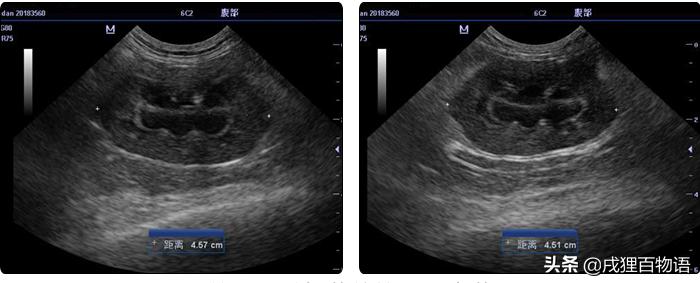

2 影像学检查

检测出蛋蛋双肾髓质环征、肾盂积液、膀胱未见明显异常。